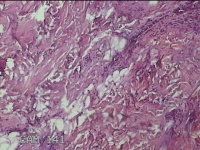

右侧颜面部结节

性别

男

年龄

49岁

临床诊断

皮脂腺囊肿

一般病史

发现右侧颜面部结节5年余。

标本名称

大体所见

灰白暗红色组织1x0.7x0.3cm一块,表面带梭形皮肤1x0.5cm,皮下见结节0.9x0.7x0.3cm一个,切开结节呈实性,切面灰白暗红色,质中。